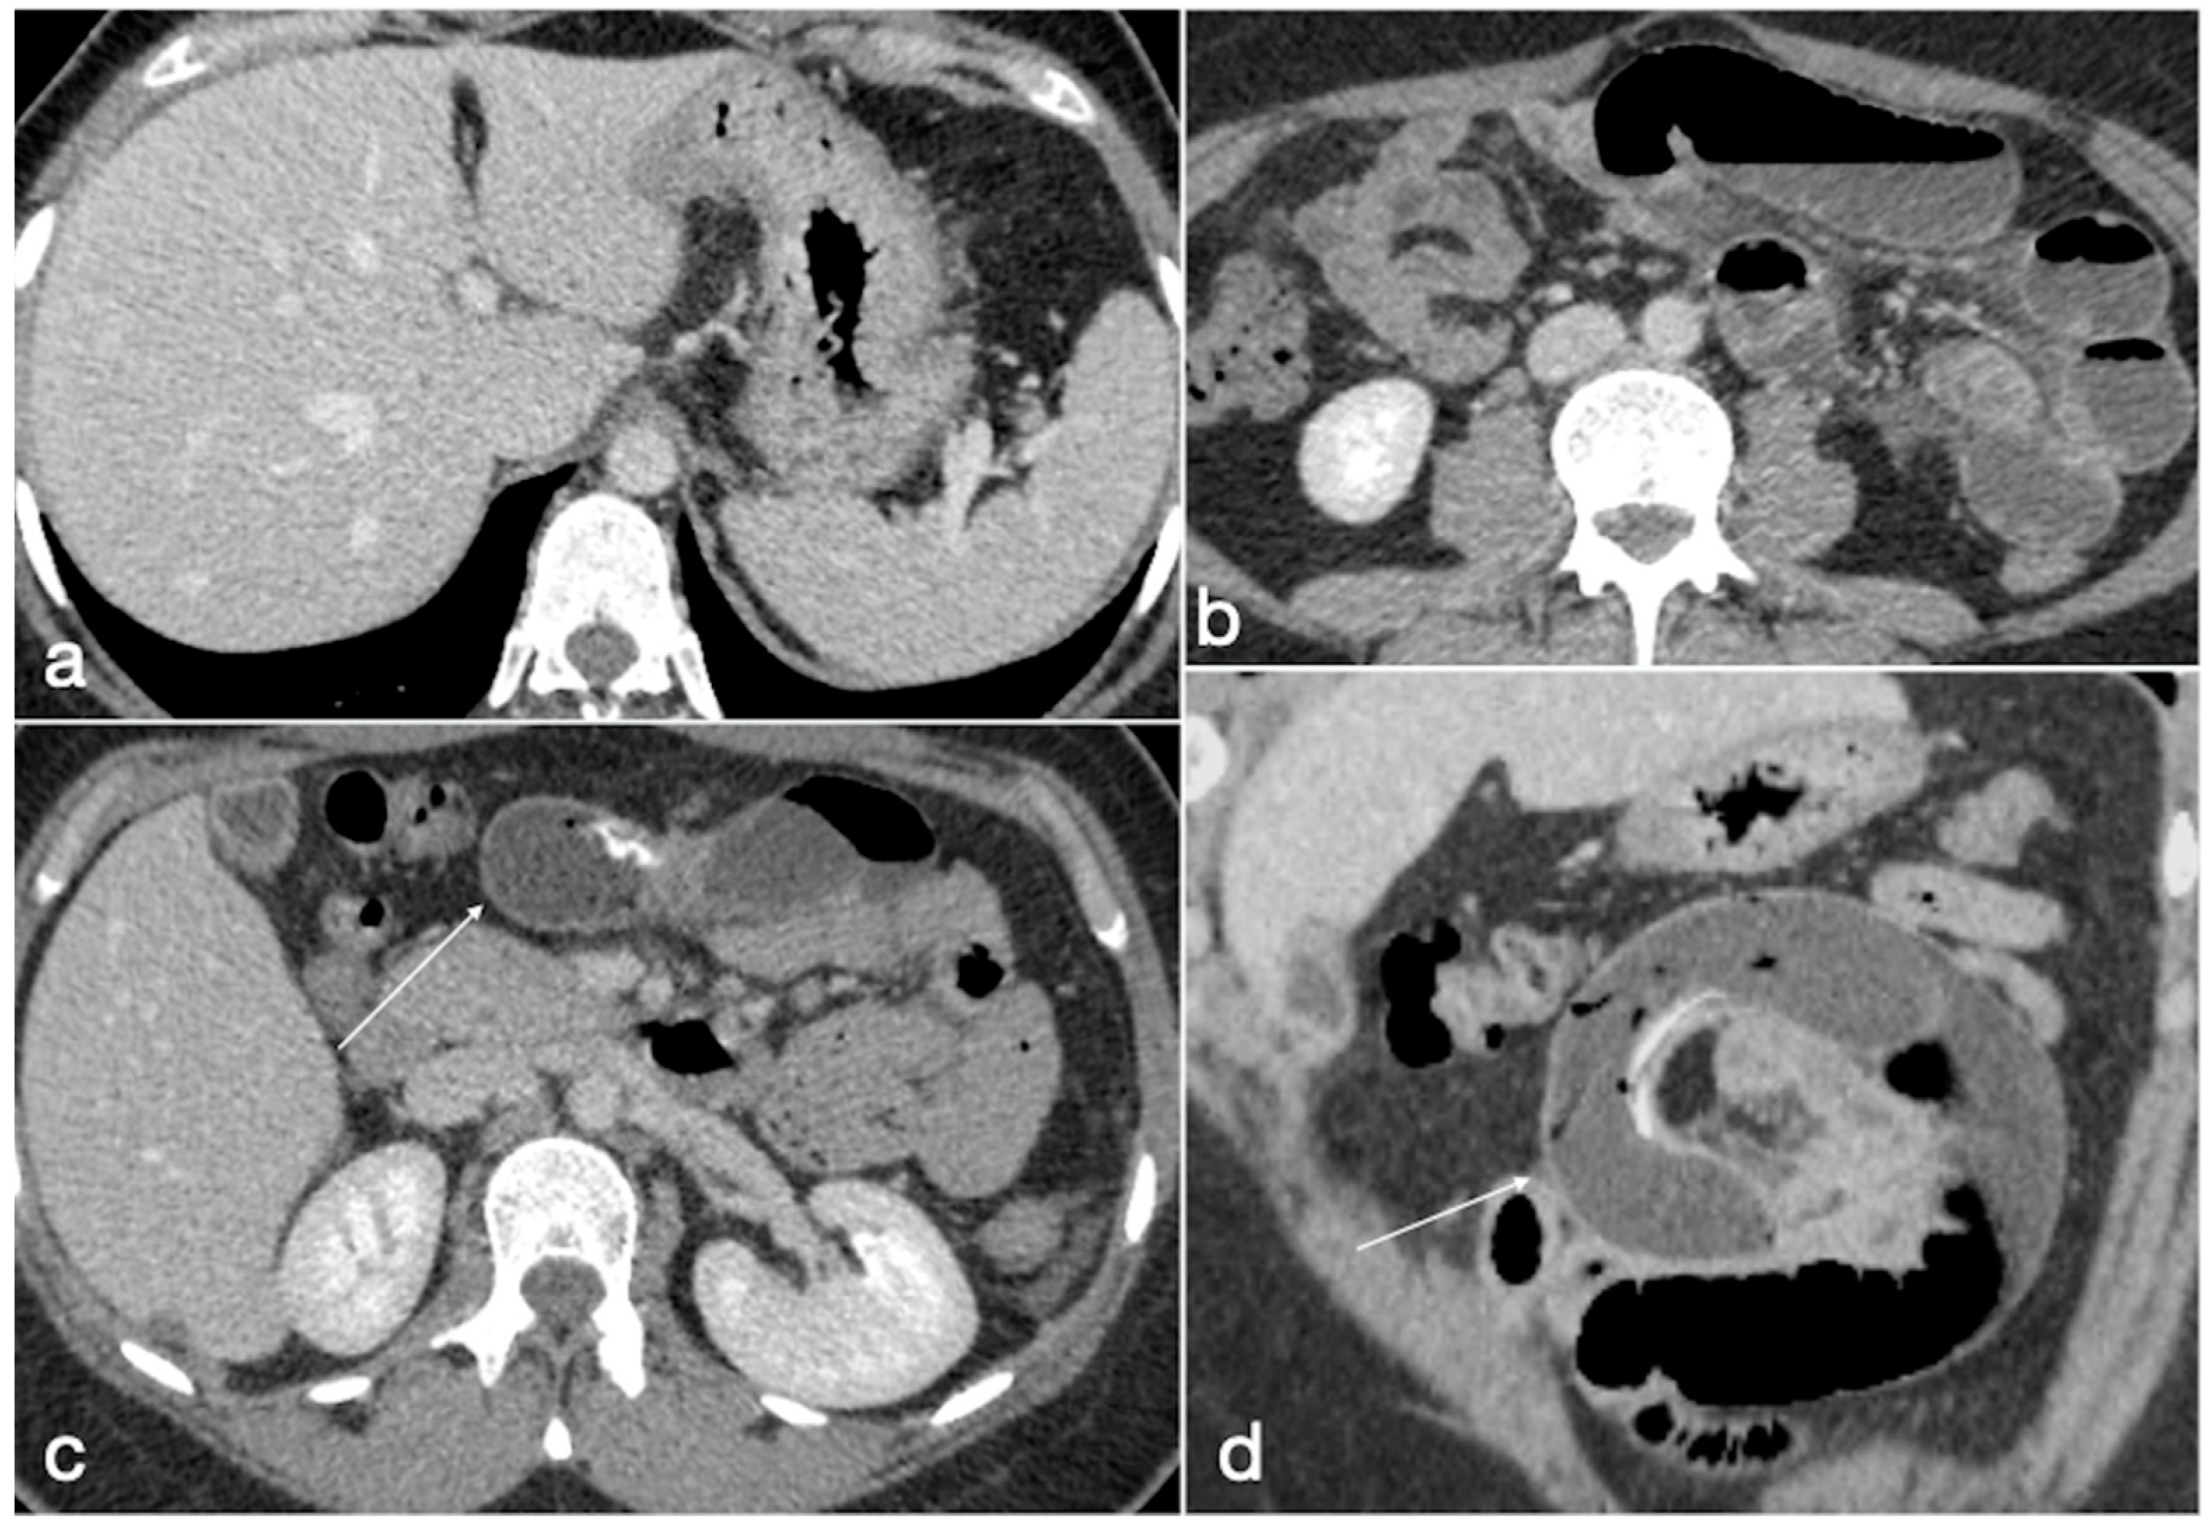

- Internal hernia